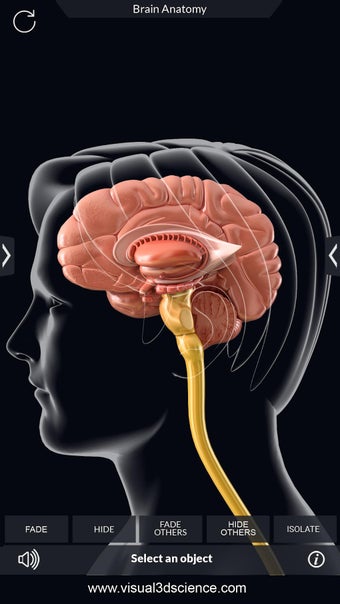

برنامج تشريح الدماغ Pro هو تطبيق تعليمي لدراسة تشريح الدماغ البشري. تم تصميم هذا التطبيق لكل من الطلاب الطبيين والجمهور العام. يتيح للمستخدمين استكشاف الدماغ من جميع الزوايا وعرض التشريح بطرق مختلفة. إنه أداة سهلة الاستخدام تتيح للمستخدمين تدوير 360 درجة والتكبير والتصغير وتحريك الكاميرا حول نموذج ثلاثي الأبعاد واقعي للغاية. يتيح للمستخدمين القدرة على تحديد الأجزاء وعرضها بالأشعة السينية وإخفائها وإظهارها وعرض الرسوم المتحركة في الوقت الحقيقي والرسم أو الكتابة على الشاشة ومشاركة لقطات الشاشة ونطق الصوت لجميع مصطلحات التشريح والمزيد. إنه تطبيق تعليمي مجاني.